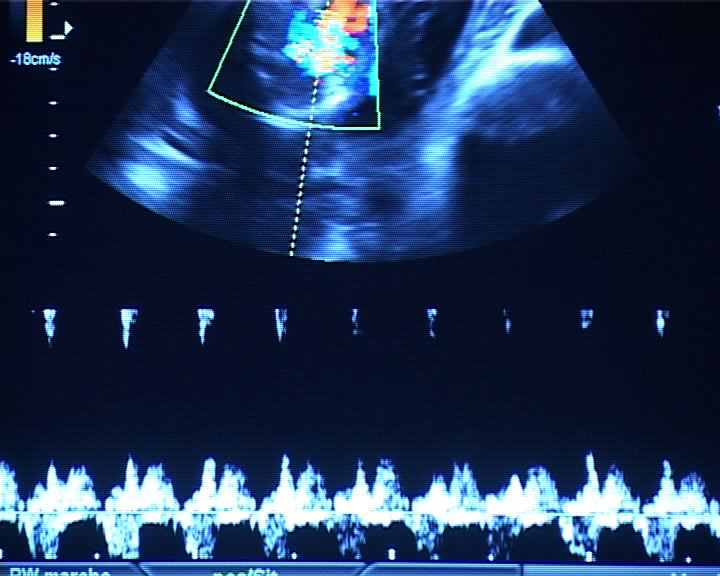

Que se passe-t-il derrière ces portes, ces couloirs d'hôpital aux couleurs saturées ? Qu'éprouve-t-on à cet endroit, avec ces jeunes femmes en tenue rose passé, dans le battement et le souffle des machines, la douleur ? Parmi les tuyaux, les poches, les lumières, les chiffres et les tracés des appareils et des alarmes ? Les cris, l’abstraction des vocables techniques, les tensions, les frottements, et la douceur aussi des gestes silencieux ? Quels interstices faut-il regarder pour assister à une cérémonie secrète faite de douleur, d'efforts, de concentration, de rythmes qui s'accélèrent, de voix qui encouragent, et où la délivrance ne va pas sans le regard d’adieu minutieux à ce qu'on doit laisser ?